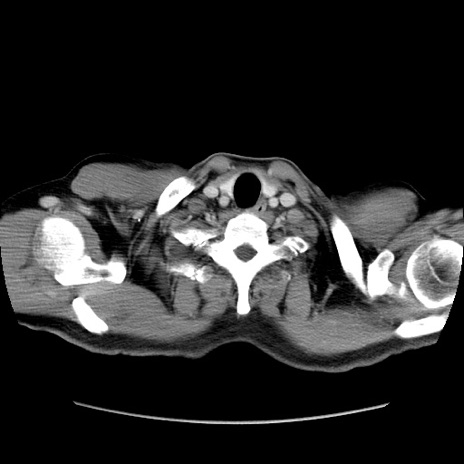

冠状断像